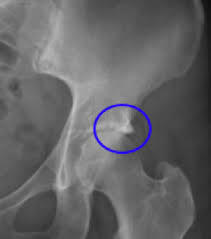

Pincer lesion

acetabulum extends out too far and “pincers” the femoral head causing FAI

CAM lesion

“knuckle” of bone coming out of the femoral neck seen in FAI